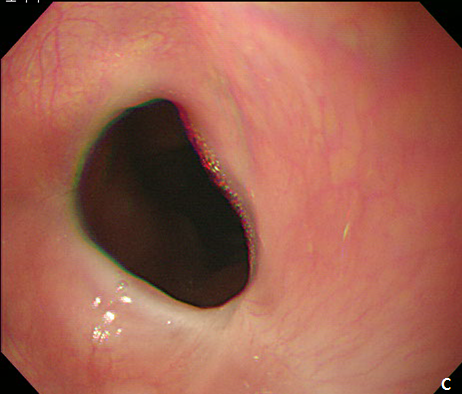

A 61-year -old woman was refferred to our hospital for further evaluation of esophageal SET. She hassuffered fromdysphagiafor many years, and an EGD showed a large, 3.5 cm sized, elongated SET at upper esophagus, 22 cm from incisor, and it showed positive rolling sign (Figure 4). As the conventional ESD is expected to cause post-procedural stricture of esophagus, we decided to perform subepithelial tunnelling endoscopic resection (STER) method to preserve mucosal integrity and prevent stricture. STER was performed according to previously suggested protocols.3 Briefly, a mixed solution of epinephrine in saline (1:10,000) was injected at submucosal layer, and a 2.0cm longitudinal mucosal incision was made to gain entry to the submucosal area and a submucosal tunnel was created 5.0 cm proximal to the SET until the tumor was visible by an endoscope while carefully preserving the covering mucosal integrity After exposure of the SET, complete dissection of the tumor was carefully performed using an IT knife along the margin. After dissection, mucosal integrity was preserved well, and the mucosal entry site was closed with standard hemostatic clips (HX-610-90, Olympus Optical Co Ltd.) (Figure 5A-5D). The resected specimen was 3.5 cm in length and 1.7 cm in diameter, and tumor was diagnosed as leiomyoma by histopathologic examination. The patietns had no immediate major complications, and discharged 3 days after the procedure. A follow-up EGD was performed at 6 and 24 months after the procedure, which showed no significant stricture, and only scar change was noted on the mid esophagus (Figure 6).

Figure 4 A large esophageal subepithelial tumor (SET).

An esophagogstroduodenoscopy (EGD) showed a large (3.5 cm) SET at mid esophagus.